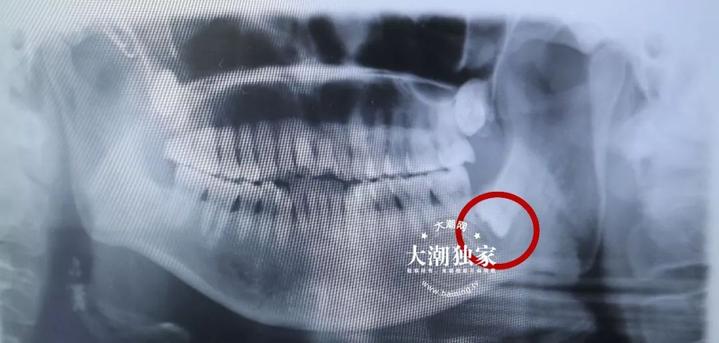

这拖下去可不是办法!于是,沈阿姨急急忙忙来到了海宁市人民医院牙科门诊,接诊的医生看了看沈阿姨的情况并结合口腔全景片,当下就对沈阿姨说:“拖不得!得赶紧做手术!”

原来,经过检查,医生发现沈阿姨的智齿下面长了一颗蚕豆大小的囊肿,就长在颌骨上面(颌骨是指牙床所在的骨组织),属于颌骨囊肿里的含牙囊肿。